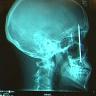

A 12 Nail Head. "An Oregon man who went to a hospital

complaining of a headache was found to have 12 nails embedded in his skull

from a suicide attempt with a nail gun.

Surgeons removed the nails with needle-nosed pliers and a drill. The

man was high on drugs when he fired the nails--up to 2" long--into his head

one by one." Ed. He survived the "shooting," but is being charged with

Building Code violations for not spacing the nails properly! |